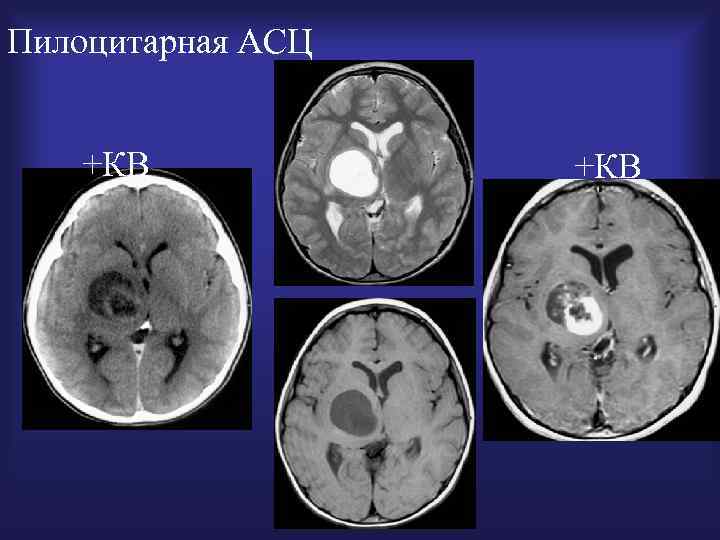

Пилоцитарная АСЦ +КВ